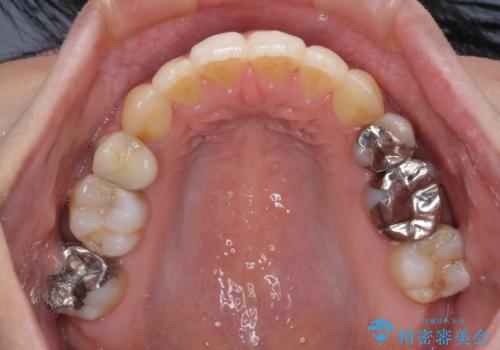

後戻りで突出した前歯をインビザラインで解消

- 抜歯矯正の後戻りで前歯が突出してきていることを気にして来院された患者様です。

口元の突出感を改善するにあたり、抜歯矯正は行うことができないため、奥歯の後方移動とIPR(歯と歯の間を削る)により達成することとしました。

再度後戻りしたときに対応しやすいよう、インビザラインにて矯正治療を行うこととしました。

舌の突出癖がなかなか改善できず、IPRによる前歯の隙間が閉じきらずに、予定よりも長い治療期間となりました。